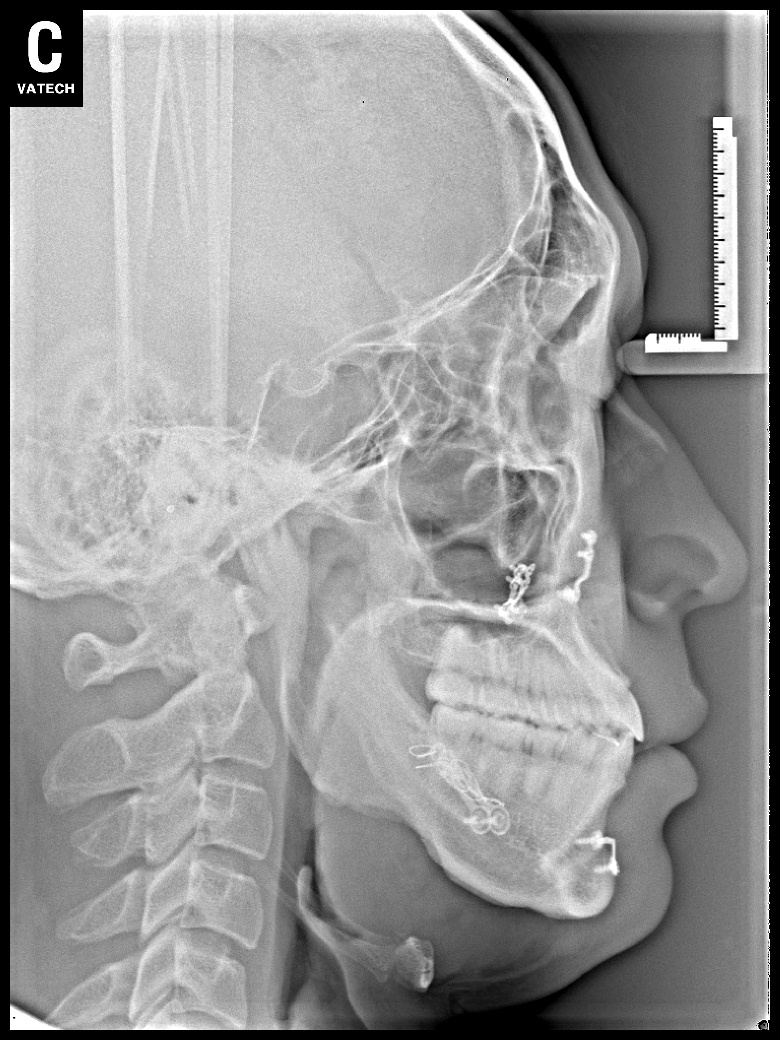

치료 전 사진입니다.